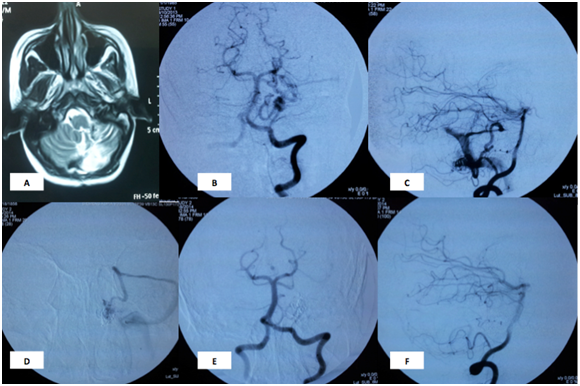

Figure 1 Case 1: A 28 years old female patient presented during the second month of pregnancy with acute hemiataxia. MRI brain showed Left cerebellar hematoma. DSA showed Lt hemispheric cerebellar AVM supplied by hemispheric branches of Posterior Inferior Cerebellar Artery (PICA). Onyx and NBCA embolization was done in two sessions with eventual complete obliteration and marked symptomatic improvement 6 months later.

Conventional angiogram during embolization procedure: A: MRI shows resolving cerebellar hematoma, B&C: AP and lateral views of the left vertebral artery showing the Lt hemispheric cerebellar AVM nidus supplied by hemispheric branches of Posterior Inferior Cerebellar Artery (PICA) and superior cerebellar artery D: microcatheter is inside the AVM nidus. E&F: AP and lateral views showing disappearance of the nidus.